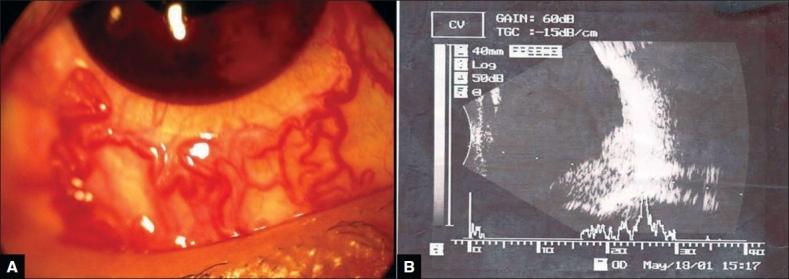

An 18-year-old boy presented to us with bilateral retinal hemangioblastoma and von Hippel-Lindau disease with history of cerebral capillary hemangioblastoma and embryonic cell carcinoma of left testes. The vision in the right eye was already lost with development of secondary closed angle glaucoma, optic atrophy with subsequent development of bullous keratopathy. The multiple retinal angiomatous lesions in the seeing left eye were treated with various modalities like triple freeze thaw cryopexy, focal lasers and transpupillary thermo therapy in multiple sittings over a period of almost 20 years since detection. One particular angiomatous lesion in the left eye was showing resistance to all the above mentioned modalities and was finally successfully treated with verteporfin and photodynamic therapy to achieve complete regression without any post-treatment complication and with a sustained 20/20 vision till a follow-up of 15 months.

一位 18 岁男孩因双眼视网膜血管瘤和 von Hippel-Lindau 病就诊,他曾患有脑毛细血管血管瘤和左侧睾丸胚胎细胞癌。右眼视力已经丧失,继发闭角型青光眼,视神经萎缩,随后出现大疱性角膜病变。左眼多发性视网膜血管瘤病变在过去 20 年中通过多次治疗,包括三重冷冻-解冻冷冻消融、局部激光和经瞳孔热疗等方式进行治疗。左眼的一个特定的血管瘤病变对上述所有治疗方法均有抵抗,最终成功地使用维替泊芬和光动力疗法进行治疗,达到完全消退,无任何治疗后并发症,随访 15 个月时视力持续保持 20/20。